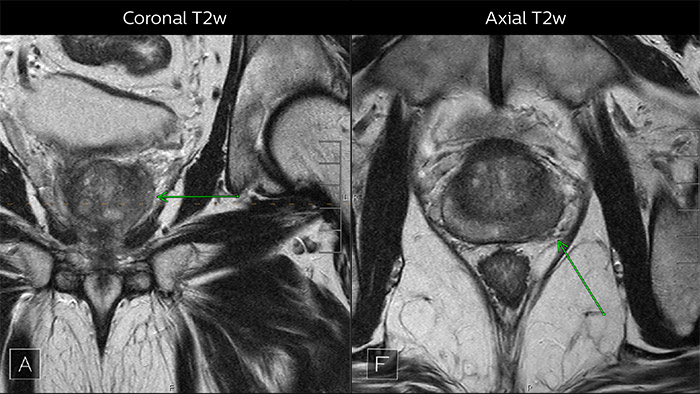

For lesions in the prostate’s peripheral zone, the DWI (diffusion weighted imaging) and ADC map are most helpful for our diagnoses. In this case, the DWI shows very bright signal, which indicates diffusion restriction. The arcuate area with significant signal drop out (arrow) on the ADC map is recognized as highly suspect for tumor. On the axial T2- weighted image the capsule contour looks a little irregular (arrow), which we interpret as capsular disruption and I usually give a measurement: this lesion shows larger than 1.5 cm capsular disruption. I don’t see any signs of lymphadenopathy, but interpret this lesion as PI-RADS 5. The hypervascular flow pattern in the bottom images adds to the diagnostic confidence.